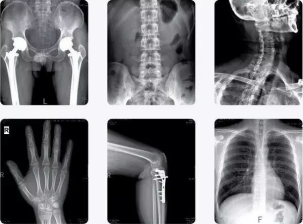

医幼场馆中心校医院购置一套医用X线摄影(DR)系统

本学期,我校校医院坚持提高自身的医疗技术水平,以不断加强医院建设,积极更新陈旧设备,近日新添置了一套更为高精的DR(医用X线摄影系统)医疗设备。

这标志着我院医学X射线检查技术己进入全新的数码时代

诊疗技术水平再上新台阶!

数字化医用X射线摄影系统DR设备

我院引进的全新数字化X线摄影拍片系统,可为检查者提供从头至脚的X射线检查,表现为以下几大特点

第一 图像分辩率高覆盖更大

DR透射过人体后的X射线探测信号被关联的计算机获取,直接形成数字影像,图像层次更加丰富,图像清晰、细腻、对比度高。具备高级临床应用功能:ATH组织均衡(可为临床提供图像质量更高的影像,提高病变检出率),实现了人们梦寐以求的模拟X射线图像向数字化X射线图像的转变。

DR设备 通过大范围8方向悬浮床板达到便捷优秀的摆位,无论是颈、胸、腰、腿等常规体位还是特殊投照体位的拍摄,均可轻松完成。患者在检查过程中无需过多移动便可进行多种检查,方便我校离退休教职工,特别是高龄老人健康检查时的需要。